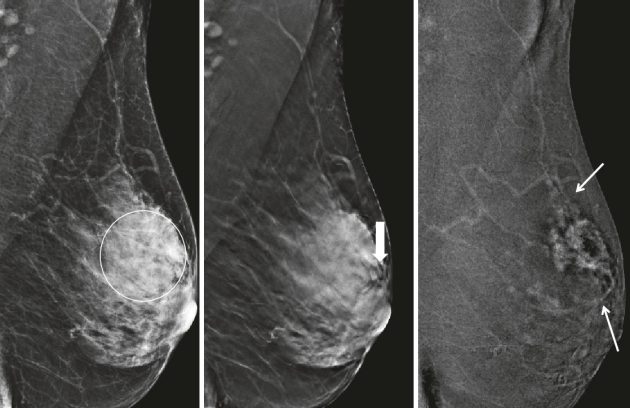

بهترین مرکز ماموگرافی در تهران

ماموگرافی پستان با بیمه بانک تجارت

ماموگرافی پستان با بیمه بانک تجارت ماموگرافی پستان با بیمه بانک تجارت | سونوگرافی رادیولوژی شرق ماموگرافی پستان یکی از مهمترین…